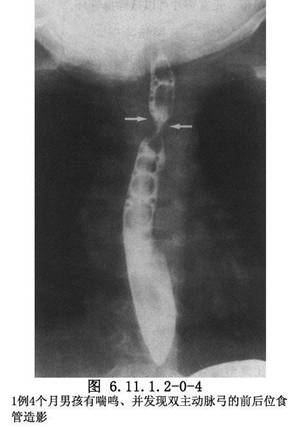

双主动脉弓影像表现见下图(图6.11.1.2-0-3,6.11.1.2-0-4)。